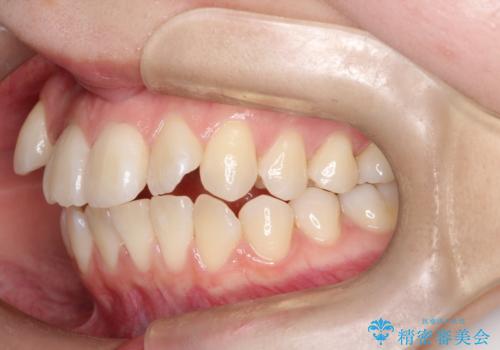

ハーフリンガル矯正|下顎前歯3本の特異症例を抜歯矯正で改善

- 患者様は下顎の前歯が3本しかないという特異な歯列を持ち、噛み合わせのバランスが崩れていました。上下の歯の本数が通常と異なるため、抜歯部位の選定が重要となるケースでした。診査の結果、歯の位置や咬合のバランスを考慮し、上顎の両側小臼歯2本と左下の小臼歯1本を抜歯することで、上下の噛み合わせを整える方針としました。矯正装置は、**目立ちにくいハーフリンガル(上顎は裏側矯正・下顎は表側矯正)**を採用しました。

まず、計画通りに抜歯を行い、歯列のスペースを確保しました。上顎は裏側矯正(リンガル)で目立たないように配慮しながら歯を後方へ移動し、下顎は表側矯正を使用して、3本の前歯の位置関係を調整。上下の歯の噛み合わせを細かくコントロールしながら、全体のバランスを整えました。治療後は「歯並びがきれいになり、噛み合わせもしっかり合うようになった」と患者様にも満足していただけました。